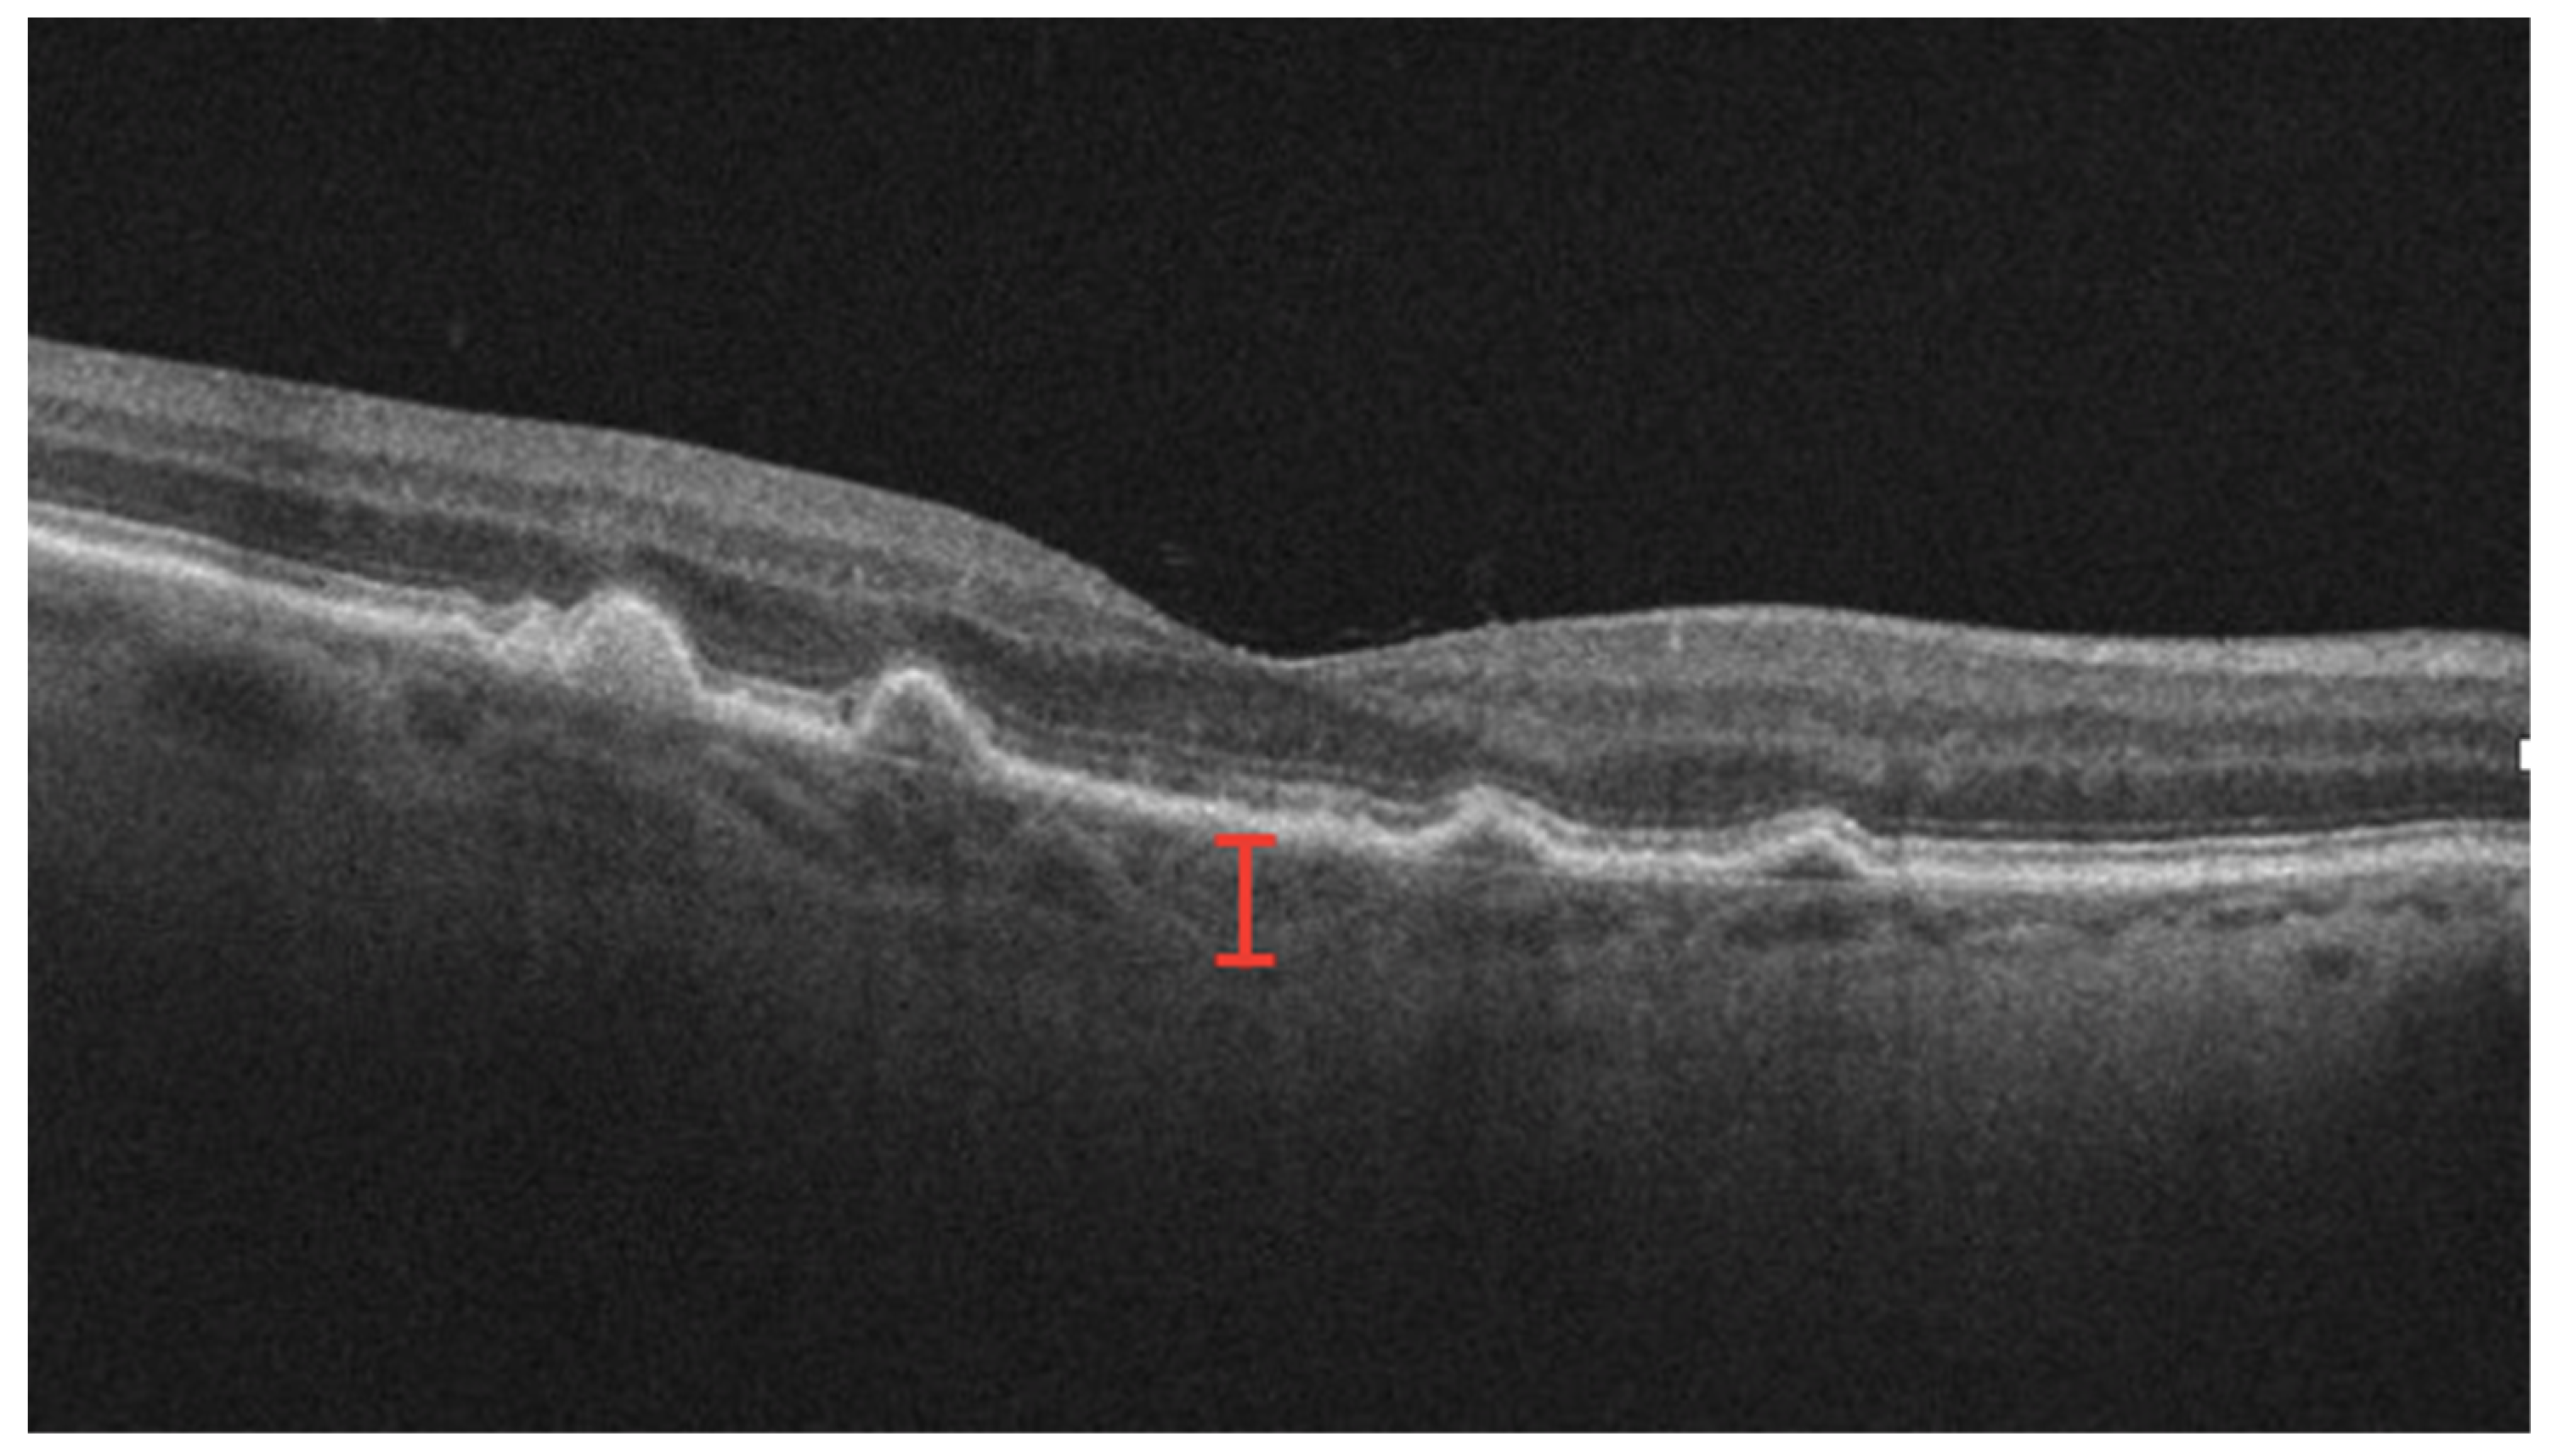

3.8. Choroidal Thickness

Significant research has focused on understanding the utility of choroidal thickness, particularly subfoveal choroidal thickness (SFCT), as a predictor of the nAMD course and prognosis (Figure 6). Studies have investigated the effects of both SFCT at baseline and changes in SFCT over disease course [74,75]. Most studies demonstrate that an increased SFCT at baseline is associated with better visual outcomes [76,77]. A thicker SFCT is hypothesized to represent preserved choroidal function and better retinal nutrition, while a thinner SFCT may denote choroidal atrophy and loss of function in chronic disease. However, existing literature does not reach a consensus on SFCT at baseline, as other studies have demonstrated an increased need for anti-VEGF treatment in patients with a thicker choroid, as well as no significant relationship between the SFCT and VA [78]. Much of the current literature on changes in choroidal thickness has focused on changes following anti-VEGF [79,80]. That anti-VEGF injections result in decreased choroidal thickness is well known, but literature is mixed as to whether the subsequent decrease in choroidal thickness is associated with an improved VA, as some studies report a significant improvement in VA, while others report no significant relationship [81,82]. Therefore, it is unclear if anatomic changes in choroidal thickness result in improved visual outcomes.

Figure 6.

OCT with subfoveal thickness measurement demarcated by red lines spanning from retinal pigment epithelium to sclerochoroidal interface.